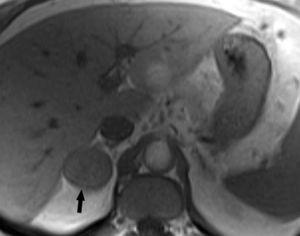

Metástasis hepáticas y suprarrenales

La aparición de nódulos suprarrenales se da en más del 10% de los pacientes con cáncer de pulmón. Dada la elevada frecuencia de adenomas benignos, es crucial la distinción entre éstos y la afectación metastásica. Ésta se puede llevar a cabo con una combinación de estrategias de imagen que incluyen TC, RM y/o PET. Por TC los adenomas suprarrenales típicamente tienen valores de atenuación bajos por la presencia de cúmulos lipídicos. Una lesión suprarrenal con valores de atenuación menores de 10 unidades Hounsfield (UH) en el estudio sin contraste, tiene una probabilidad del 98% de que se trate de una lesión benigna. Dado que ambas lesiones, adenomas y metástasis captan contraste, la valoración rutinaria de la captación no es útil en la diferenciación entre benignidad y malignidad. Si se detecta durante la realización de la TC, realizar cortes tardíos a los 15 minutos de la administración de contraste es importante, ya que si existe un lavado del contraste de más del 50% el diagnóstico de adenoma tiene una sensibilidad del 98% y una especificidad que oscila entre el 92 y el 100%20. La RM con secuencias de desplazamiento químico en la valoración de nódulos suprarrenales tiene una especificidad del 100% para el diagnóstico de adenoma (fig. 14). Sin embargo, la sensibilidad depende de la densidad de la lesión en el estudio con TC, ya que cuanto mayor es la densidad en la TC menos señal perderá en la RM, con lo que resulta más difícil etiquetarlo como adenoma21. La PET presenta una sensibilidad alta en la detección de metástasis suprarrenales, ya que cuando una lesión suprarrenal no muestra signos concluyentes en la TC de benignidad, la ausencia de actividad con la PET hace muy probable dicho diagnóstico. En los casos en que persistan dudas diagnósticas se debe recurrir a la biopsia de la lesión adrenal, especialmente si de este diagnóstico depende el manejo del paciente.

Fig. 14.--Lesión suprarrenal. (A) Tomografía computarizada (TC) abdominal sin contraste que muestra un nódulo suprarrenal derecho de baja atenuación y contornos bien definidos (flecha). (B) Con contraste se aprecia captación del mismo. (C) Resonancia magnética (RM) en fase en la que se identifica el nódulo suprarrenal isointenso con el hígado. (D) En la RM fuera de fase, se pone de manifiesto la pérdida de señal (marcadamente hipointensa con respecto al hígado) característica de estos tumores suprarrenales debido a su contenido lipídico.